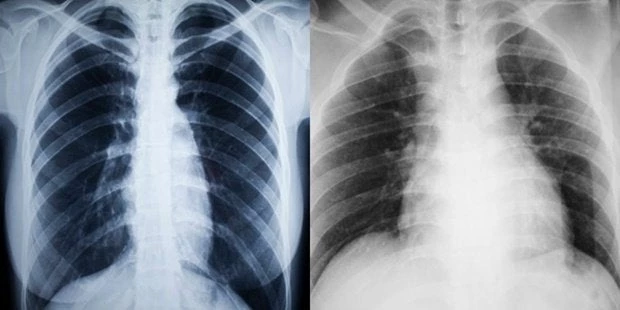

Αντέχεις να αντικρίσεις την πραγματικότητα; Δες τι κάνει το κάπνισμα σε σένα και όσους αγαπάς (Εικόνες – Βίντεο)

Καθημερινές είναι οι εκκλήσεις προς τους καπνιστές να σταματήσουν να καπνίζουν. Δεν είναι μόνο ότι το τσιγάρο προκαλεί μόνιμη βλάβη στους πνεύμονες, αλλά μπορεί να προκαλέσει ακόμη και μ...